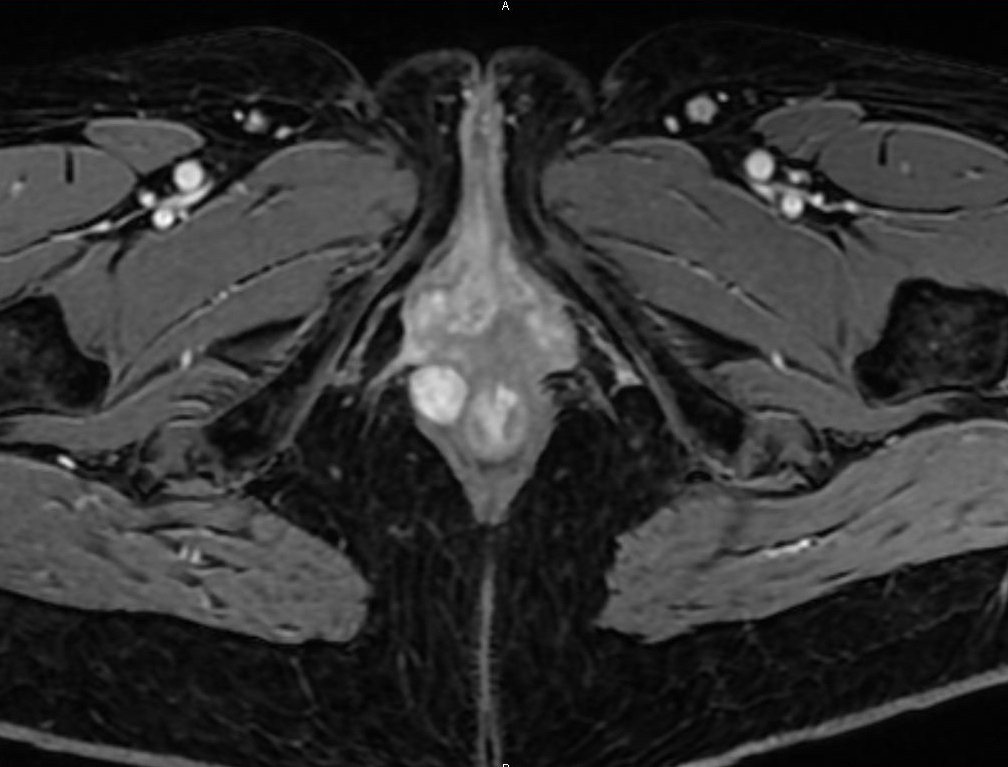

Un homme de 58 ans consulte pour une sensation de masse anale. L’inspection retrouve une tuméfaction sous-cutanée de la marge (fig. 1).

Souvent asymptomatique, cette tumeur peut provoquer une sensation de corps étranger ou une gêne à la défécation. Elle est parfois découverte de façon fortuite, lors d’une endo­scopie ou d’une chirurgie, par exemple. La masse est ferme, bien limitée, souvent mobile à l’examen clinique. L’imagerie par endosonographie et/ou IRM (fig. 2) permet de préciser les rapports avec le sphincter et d’éliminer un léiomyosarcome (aspect hétérogène, envahissement, nécrose).